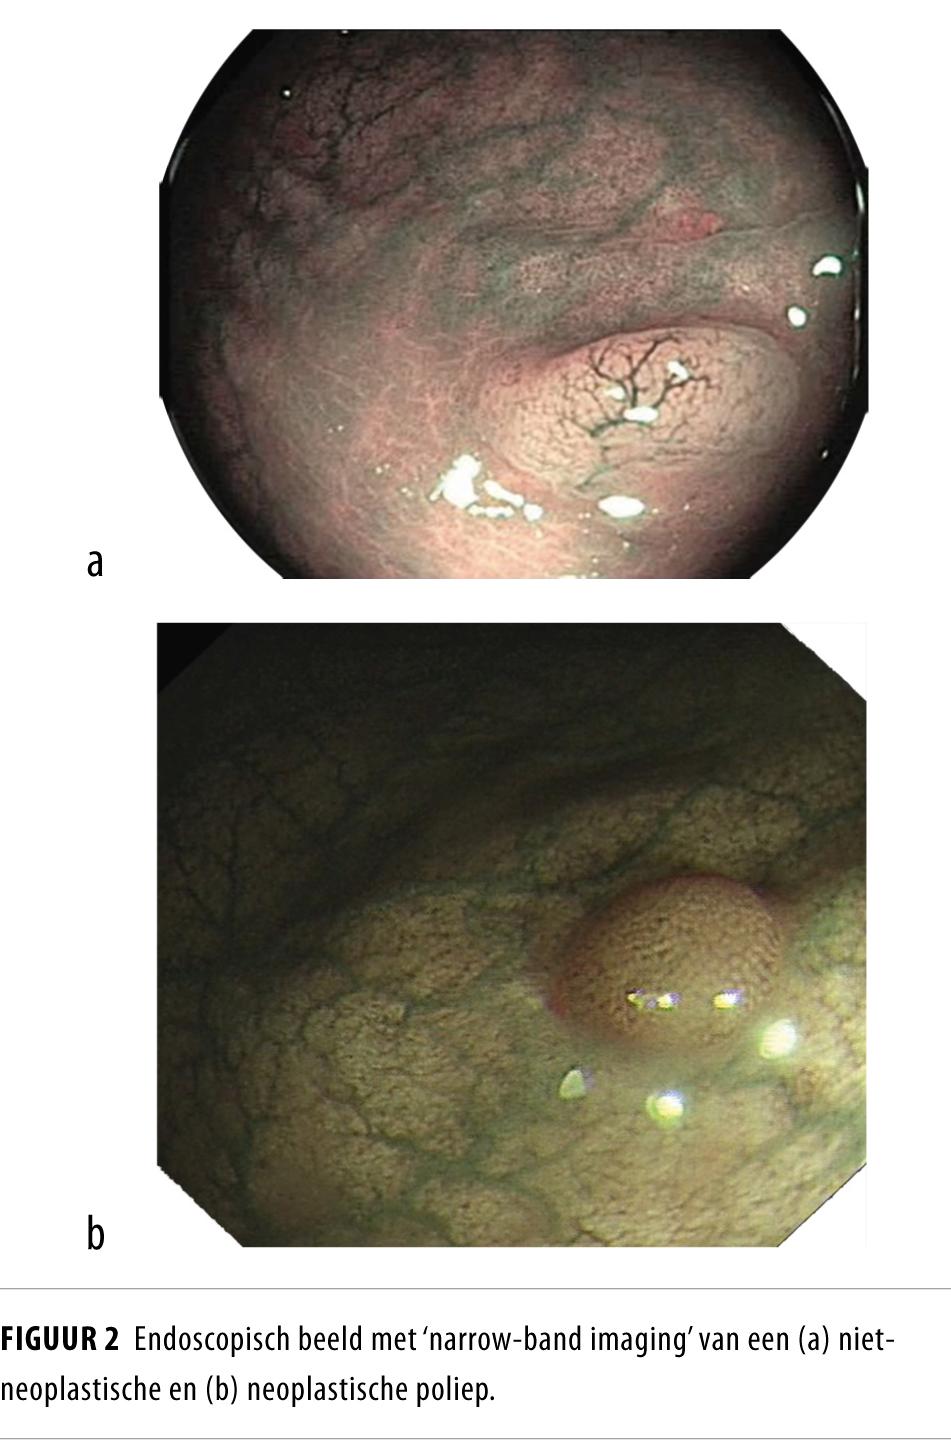

Bij een coloscopie worden vaak poliepen van 1-5 mm groot gevonden. Deze blijken slechts sporadisch kwaadaardig te zijn. Het verwijderen, verzamelen en beoordelen door een patholoog van deze poliepen maken een belangrijk deel uit van de kosten van een coloscopie. De beoordeling door de patholoog is de gouden standaard en wordt in alle richtlijnen gebruikt voor het bepalen van het interval voor een surveillance-coloscopie. Als het echter mogelijk zou zijn om tijdens de coloscopie een betrouwbare endoscopische diagnose van een poliep te stellen, zal deze beoordeling door de patholoog niet nodig zijn. Deze strategie wordt optische diagnose genoemd. Toepassing hiervan kan in Nederland tot een kostenbesparing leiden. Voordat deze strategie veilig in de praktijk toegepast kan worden moet er aan minimale eisen van nauwkeurigheid worden voldaan. Met gebruik van wit-lichtendoscopie worden deze eisen niet gehaald. De ontwikkeling van elektronische chromo-endoscopie leidt tot een betere nauwkeurigheid in de endoscopische poliepdiagnose.